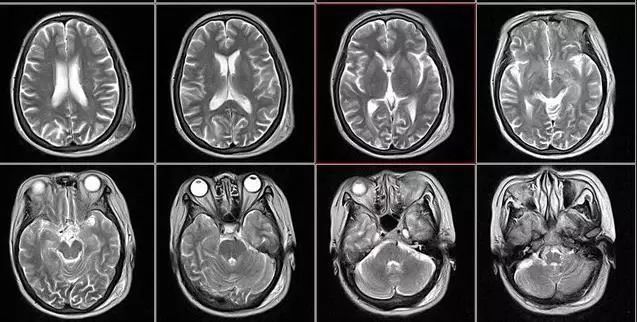

核磁共振:摇一摇再看

核磁共振机使用较强大的磁场,使人体中所有水分子磁场的磁力线方向一致,这时核磁共振机的磁场突然消失,身体中水分子的磁力线方向,突然恢复到原来随意排列的状态。简单说就相当于用手摇一摇,让水分子振动起来,再平静下来,感受一下里面的振动。所以,核磁共振(MRI)也被戏说为是摇摇看的检查。

2、颈椎腰椎——最佳选核磁、次选CT

颈椎病、腰椎间盘突出等椎间盘疾病需要观察椎间盘与相应的神经根,要想更好观察这些软组织,最优选择就是核磁。同样,对于关节、肌肉、脂肪组织检查,核磁也是首选。